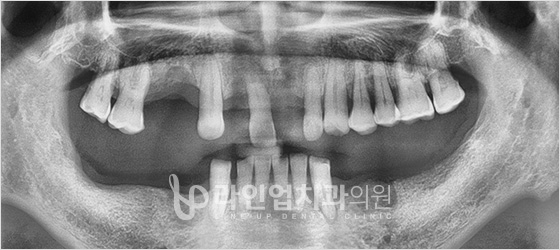

치료전 Before

치료후 After

下臼齿种植牙